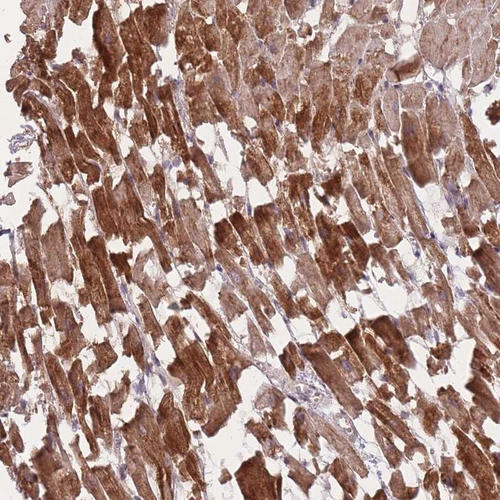

Immunohistochemical staining of human heart muscle shows strong cytoplasmic positivity in myocytes.